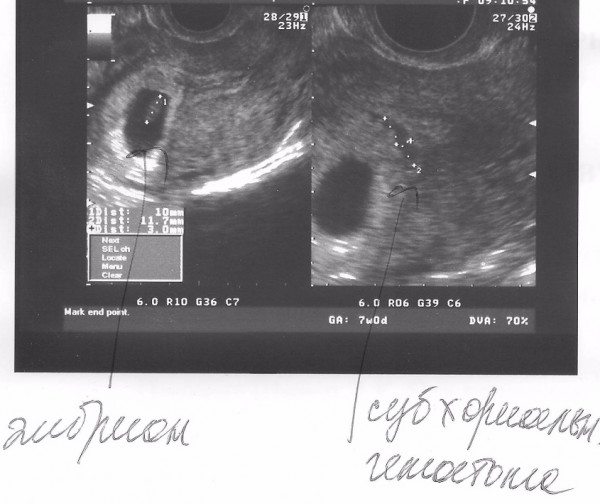

К дополнительным признакам замершей беременности относят неправильную форму плодного яйца, недостаточный прирост его диаметра в динамике, слабую выраженность децидуальной реакции, отсутствие сердцебиения на сроке гестации 7 и более недель. А признаками угрозы ее прерывания служат изменение тонуса матки и появление участков отслойки хориона с появлением субхориальных гематом.

В последующем возможно отторжение аномального плодного яйца. При этом могут быть диагностированы угроза прерывания беременности (в том числе с образованием отслаивающих ретрохориальных гематом) или самопроизвольный аборт (выкидыш). Но нередко анэмбриония диагностируется лишь при плановом обследовании, в этом случае диагноз является абсолютно неожиданным и шокирующим известием. Такая беременность требует искусственного прерывания.